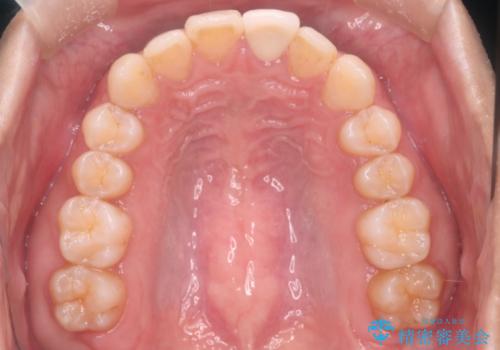

インビザラインにて治療を行うことで、前歯のがたつきが改善されました。

左上1番目の前歯はセラミックをご希望されたので、セラミックにて被せ物の治療を行いました。

とても綺麗な前歯になりました。